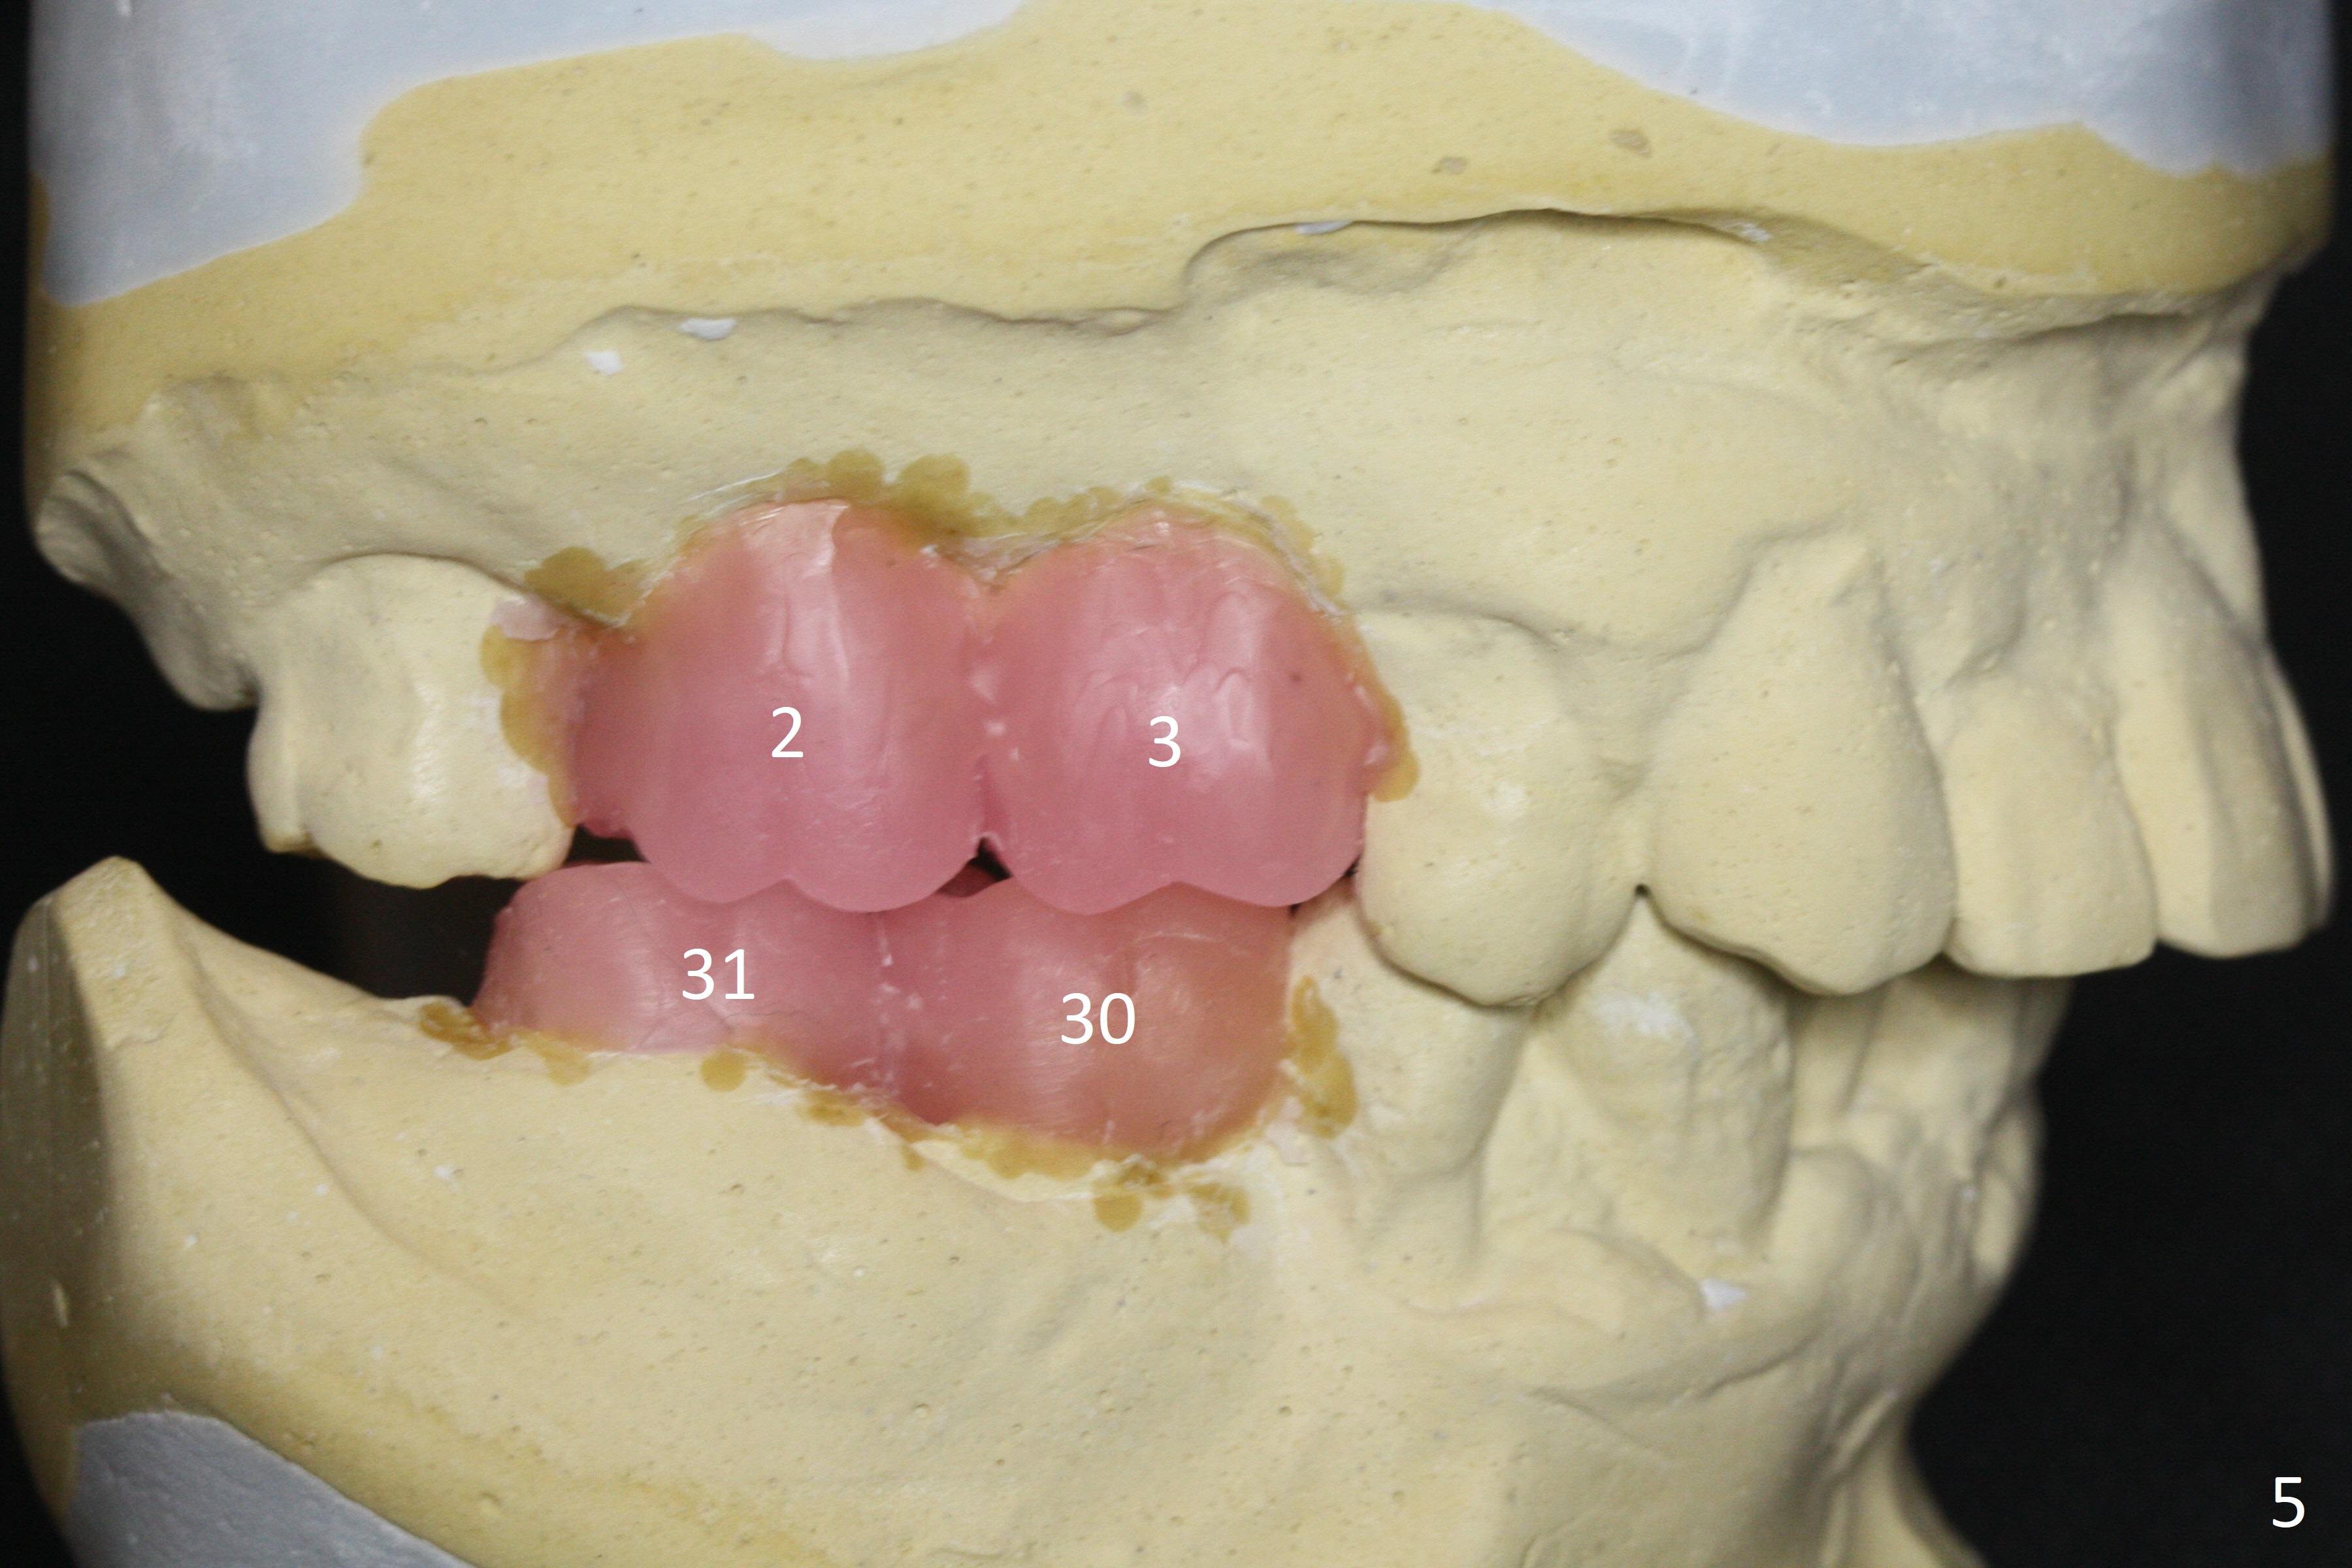

A 54-year-old man is 5 years post liver cancer surgery. After his platelet count returns normal, he wants to take care of his teeth. Most of his molars (#14, 19, 30,31) need extraction and implant placement (Fig.1-4). Although the 2nd premolars on the right are missing (Fig.1,3,4), it seems appropriate to establish 2 molar occlusion on the right (Fig.5,7,8) and 1 on the left (Fig.6,7 (because of #15 supraeruption (Fig.2 arrow))) . Since the residual roots in the lower right quadrant are irritating, implant placement will be done first (Fig.11, Clindamycin), followed by #2,3 (Fig.10) and 14(Fig.12 IBS) and 19 (Fig.12). Use IS drills and 4 and 5 mm stoppers to start osteotomy at #30 and 31, respectively.